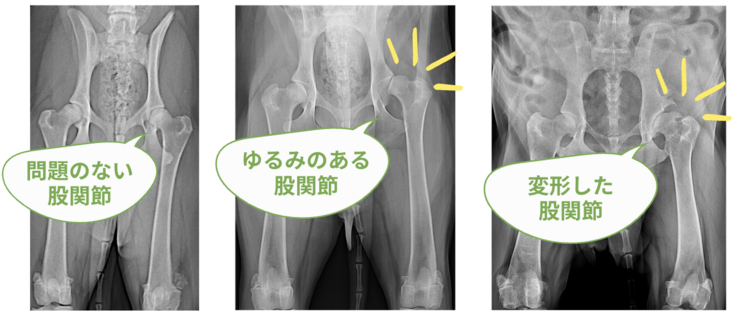

股関節形成不全は、主に大型犬種または超大型犬種に高率に発生する病気の一つで、股関節の形態的な異常に伴い関節のゆるみが生じ、二次的に関節炎や変形性関節症を引き起こすことで 跛行 を生じる疾患です。

※ 跛行(はこう):歩様に異常をきたしている状態、片足を引きずるように歩くこと。

この病気の主な症状は、足を引きずって歩いたり、後ろ足の筋肉がやせてしまうことです。子犬と成犬とで病態が異なり、子犬では、関節のゆるみが主な問題であり、成犬では、関節の変形(変形性関節症)や、炎症(関節炎)が主な問題になります。